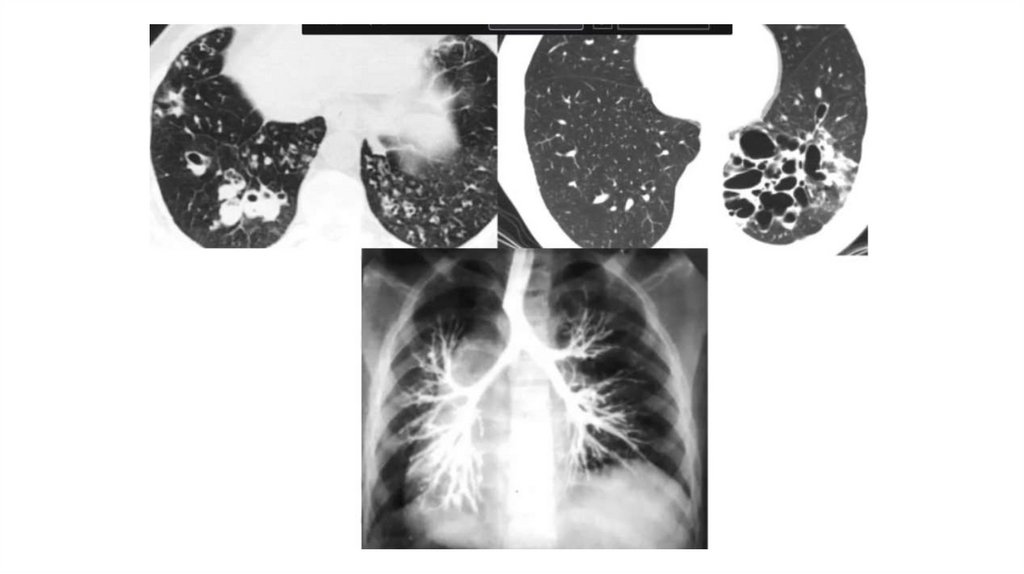

Врожденные и наследственные заболевания легких у детей